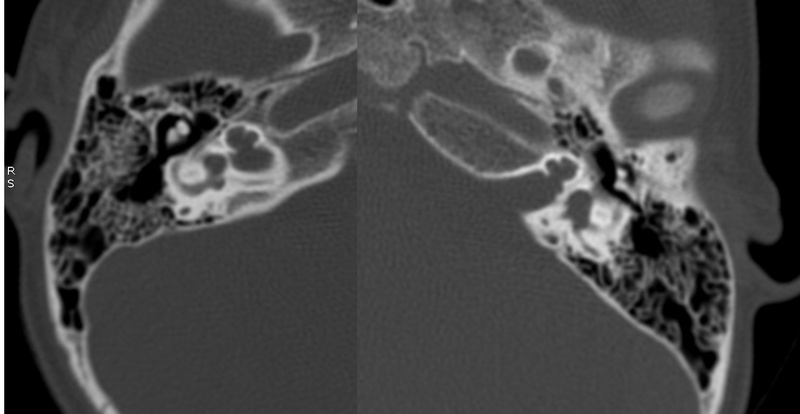

Evaluación de Imagen (TC)

Los hallazgos radiológicos, mediante TC de oídos a cuatro pacientes varones y una madre oyente, portadora obligada, se analizaron y clasificaron según Sennanoğlu et al. [8,9]. En ese sentido, son consistentes con PI-III en tres de ellos: IV-1, IV -2 y IV- 4. El paciente IV-3 mostró PI-I; la madre portadora obligada no mostró alteración alguna (Ver Tabla 3). En los cuatro pacientes estudiados de esta familia observamos dos tipos de MOI, PI-I y PI-III, incluso entre los hermanos IV-2 y IV-3, que presentaron diferente tipo de PI, lo que evidencia expresividad variable. La malformación PI-III es de las MOI menos frecuente y se encuentra presente en este estudio familiar como predominante.

Imagen 10

Corte axial de TC de ambos oídos del paciente IV-4 con PI tipo III.